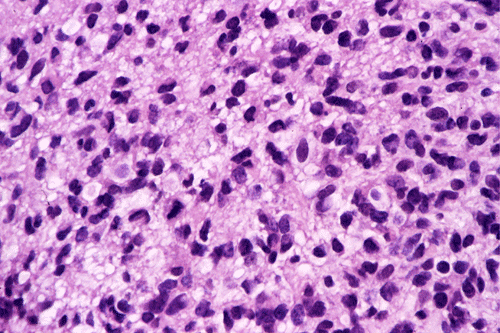

Permenant section: The pathologic changes of the permenant sections are similar to that of frozen. Again, pseudopalisading necrosis is present (Panel G and H). Many of the nuclei are elongated and there is also considerable degree of pleomorphism.  Some of the cells have perinuclear clearing (Panel I). Positive staining for glial fibrillary acidic protein (GFAP) but not synaptophysin is demonstrated by immunohistochemistry. Although the perinuclear halo may suggestive anaplastic oligodendroglioma, the overall pathologic features, particularly the elongated nuclei and degree of pleomorphism, are that of a glioblastoma.

Glioblastoma has been known as glioblastoma multiforme for many years because of its diversity in histologic appearance.. The tumor cells can vary from relatively small cells to large, pleomorphic cells to multinucleated giant cells. There is significant variation between different histologic fields and different tumors. In general, most tumor cells retain some morphologic features of glial cells particularly astrocytes. Endothelial proliferation is found in most case. Necrosis can be extensive. Pseudopalisading necrosis is a common finding and refers to necrosis, often slit like and Y-shaped, that is surrounded by fusiform tumor cells arranging in a palisading fashion. Mitotic activity varies from moderate to brisk and atypical mitoses, more commonly found in tumor with large and anaplastic cells, can be present. As per the diagnostic criteria of the World Health Organization (WHO), the presence of anaplasia, increased mitotic activity, and endothelial proliferation with or without necrosis are required for the diagnosis of glioblastoma 1.

Immunohistochemically, glial fibrillary acidic protein (GFAP) is often detectable at least focally in most cases. However, the level of expression is inversely related to the degree of anaplasia. Focal expression of cytokeratin is also present which makes cytokerain alone a relatively non-specific marker to differentiate glioblastoma from poorly differentiated metastatic carcinoma.  Immunohistochemistry for Ki67 (MIB1 antibody) will reveal a labeling index that varies from 5% to over 20%.